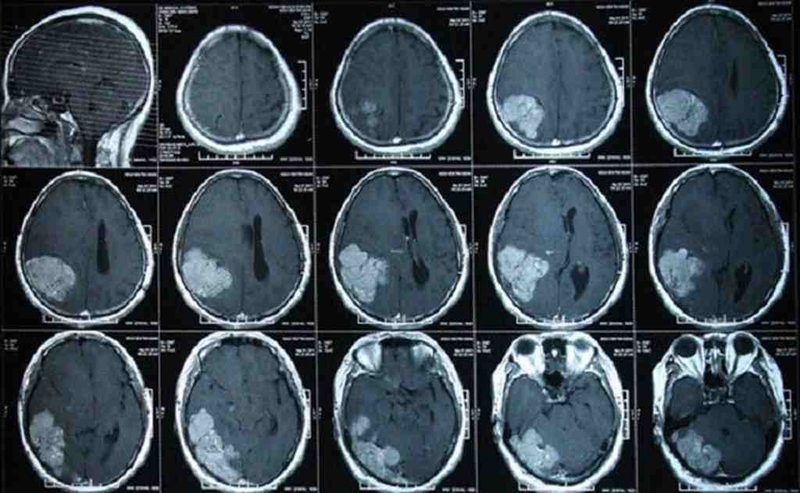

Kỹ thuật chụp CT hay còn gọi là chụp cắt lớp vi tính sử dụng đầu phát tia X quay tròn xung quanh bộ phận cơ thể cần khảo sát. Tia X sau khi chiếu qua cơ thể, sẽ đi đến bộ phận thu nhận tín hiệu (Detector) đồng thời bộ cảm biến điện tử sẽ truyền tín hiệu đến bộ phận xử lý hình ảnh để mã hóa.

Tùy từng bộ phận trong cơ thể khác nhau thì có mật độ cấu trúc khác nhau vì vậy độ hấp thụ tia X cũng khác nhau. Ở một số những bộ phận có cấu trúc đặc như các nốt vôi hóa, xương, sẽ hấp thụ nhiều tia X. Ngược lại, những bộ phận mô mềm như gan, thận, nhu mô não, tụy… sẽ hấp thụ tia X kém hơn cấu trúc đặc. Sự suy giảm về cường độ tia X sẽ được các cảm biến thu nhận và xử lý đồng thời tính toán một cách rất chính xác để tái tạo ra hình ảnh hoàn chỉnh. Như vậy sẽ giúp chúng ta dễ dàng nhận ra sự hấp thụ tia X của các cấu trúc khác nhau. Bởi vì hình ảnh sẽ có sự chênh lệch về tương phản sáng tối giữa các bộ phận trên hình ảnh CT hoàn chỉnh.

Có thể là chỉ định chụp để xác định chính xác vị trí của khối u, vị trí xương bị gãy cũng như tìm ra cục máu đông, khối máu tụ trong não, các ổ viêm, phù.

Dựa vào hình ảnh bác sĩ sẽ đánh giá tình trạng bệnh lý trong lồng ngực, ổ bụng. Ngoài ra, khi thực hiện kỹ thuật này còn giúp cho bác sĩ đưa ra định hướng chính xác khi xạ trị, sinh thiết, phẫu thuật.

Nhờ chụp CT có thể phát hiện ổ áp - xe, dị vật, hoặc các tổn thương bên trong cơ quan nội tạng như xuất huyết trong ổ bụng, chảy máu nội tạng. Kiểm tra phát hiện và theo dõi tình trạng bệnh lý như ung thư, bệnh tim mạch, các khối u bên trong gan, phổi.

Phải kể đến ưu điểm nổi bật đầu tiên của chụp CT là cho hình ảnh rất rõ nét và không có hiện tượng chồng lên nhau. Điều này giúp ích rất nhiều cho bác sĩ trong việc chẩn đoán và điều trị. Phương pháp chụp này có độ phân giải hình ảnh rõ và chuẩn hơn so với hình ảnh chụp X-quang nhiều.